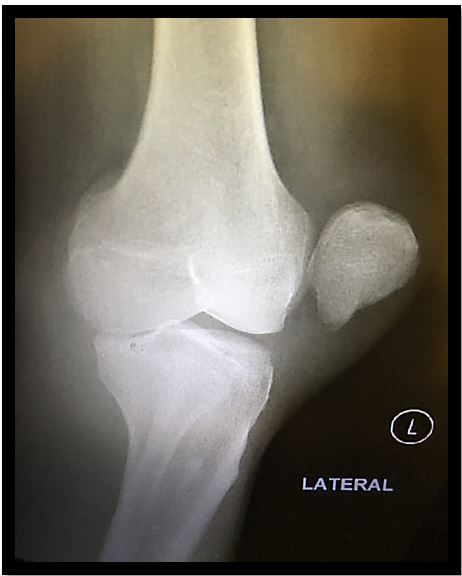

Radiograph of left knee, lateral view (Click to enlarge)

Testing. Radiograph was taken of left knee; see image at right for x-ray image (Please click to enlarge).

1. What does the case image show? A lateral patellar dislocation

X-rays in a patellar dislocation will be abnormal if the knee cap is still out of position, but even after reduction it may show small osteochondral fractures in about 35% of patients.